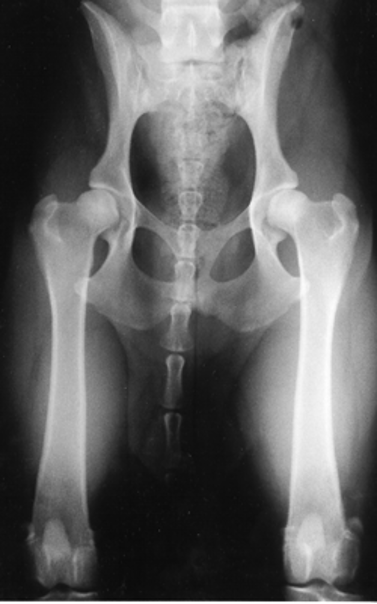

Interpreting your radiographic results

There have been multiple studies showing there is no relationship between limb function and the severity of radiographic signs. (Gordon WJ, 2003) The osteoarthritic joint does not correlate to the amount of clinical discomfort a dog has.

The hip extended ventrodorsal pelvic radiograph’s main advantage is that it gives one the ability to evaluate the joint for signs of osteoarthritis. Radiographic evidence of osteoarthritis of the coxofemoral joint includes femoral periarticular osteophyte formation, subchondral sclerosis of the craniodorsal acetabulum, osteophytes along the acetabular margin, and joint remodeling.

PennHIP distraction index is the most reliable indicator of future hip osteoarthritis, can be done as early as 16 weeks of age. 80% of dogs evaluated as “normal” by the OFA (hip -extended view) were found to have hip laxity by PennHIP testing that predisposed them to developing hip osteoarthritis in the future. (Powers MY K. G., 2010) PennHIP will enable you to guide owners on what types of activities are more suited. Will he be able to be a working or agility dog? How does the dog compare to its breed and should the dog be used for breeding? These are questions that a PennHIP evaluation can give you to help you to educate your owners on the risk of getting hip OA, managing CHD, and types of activities the dog can do.